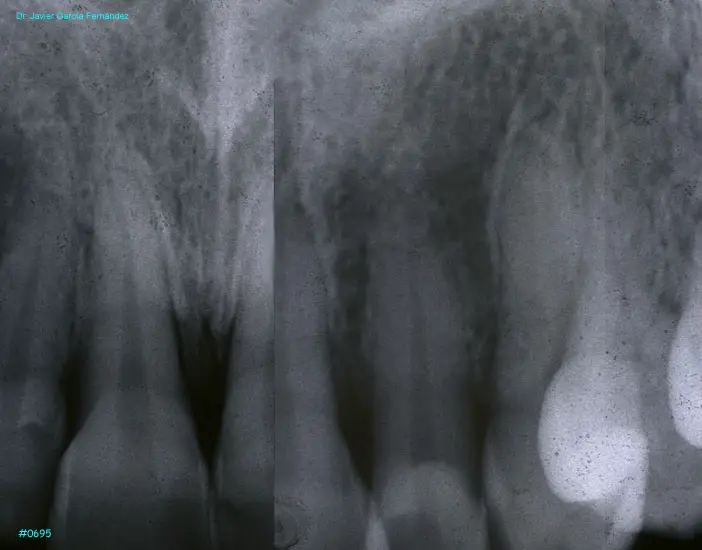

Atlas of Surgical Techniques in Periodontics. Chapter III. Atlas de Técnicas Quirúrgicas en Periodoncia